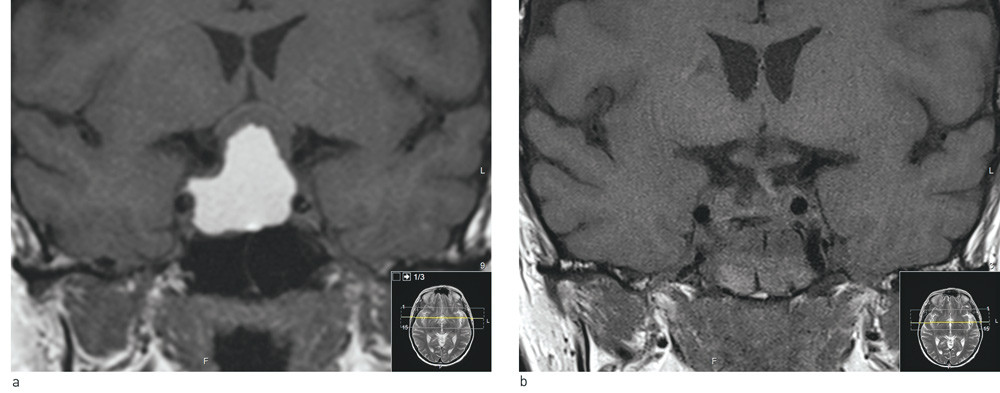

MR-undersøkelse av hypofysen (fig 1a) viste en stor (31 mm × 29 mm × 26 mm) cystisk intrasellær tumor, med en stor suprasellær komponent som løftet synsnervekrysningen. Funnet ble antatt å representere enten et kraniofaryngeom eller et cystisk hypofysært makroadenom.

MR-undersøkelse av hypofysen umiddelbart postoperativt (fig 1b) viste ingen tegn til resttumor, og det var frittliggende synsbaner. Histologisvaret viste at tumoren var et ikke-hormonproduserende hypofyseadenom med lavt nivå av proliferasjonsmarkøren ki67.